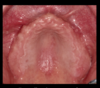

what severely compromises a denture regarding retention and stability?

if FOM is near the level of the ridge crest